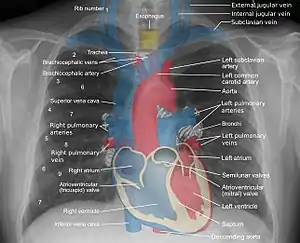

A chest radiograph, called a chest X-ray (CXR), or chest film, is a projection radiograph of the chest used to diagnose conditions affecting the chest, its contents, and nearby structures. Chest radiographs are the most common film taken in medicine.